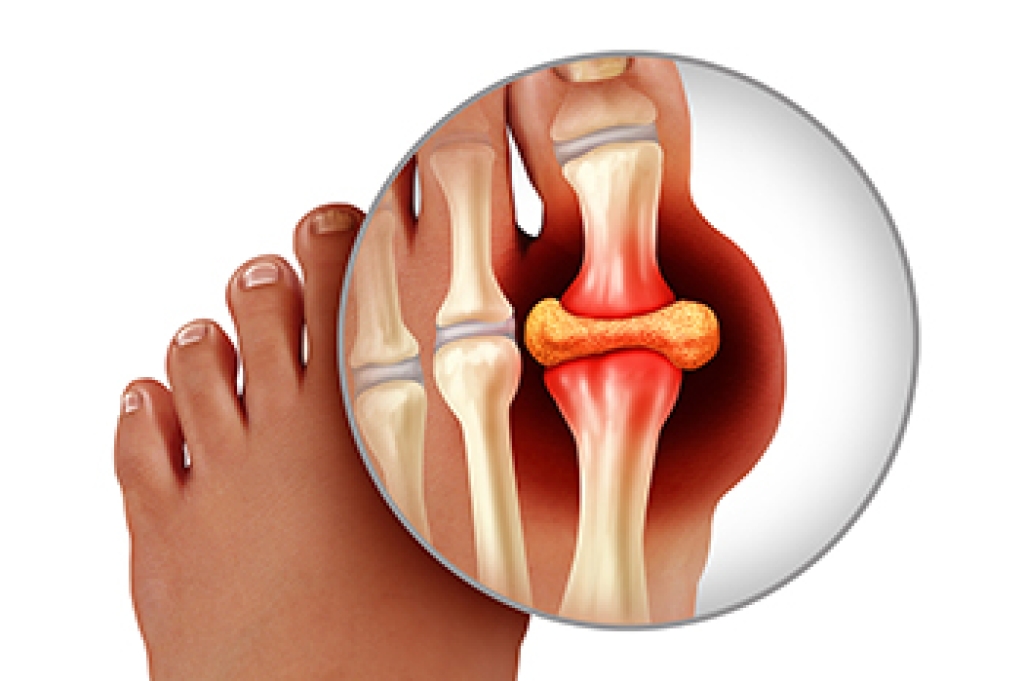

A toe fracture is a break in one or more of the small bones in the toes, usually caused by direct trauma, such as stubbing the toe or dropping a heavy object on the foot. These injuries are common and can vary in severity. Symptoms may include sharp pain, swelling, bruising, and difficulty in walking. In some cases, the toe may appear crooked or deformed. Risk factors include weak bone density, participation in contact sports, and walking barefoot in unsafe areas. A podiatrist can provide a thorough evaluation and determine the best treatment to ensure proper healing. If you think you may have fractured your toe, it is suggested that you consult a podiatrist who can accurately diagnose and treat this injury.

Severe toe fractures may be treated with a splint, cast, and in some cases, minor surgery. Due to its position and the pressure it endures with daily activity, future complications can occur if the big toe is not properly treated.